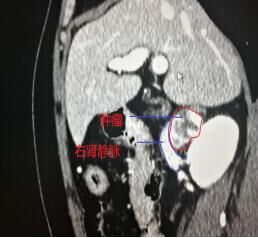

经过12天的充分术前准备,5月12日,由省立医院熊晖教授与副主任医师潘美洲主刀,为患者在全麻下行经腹腹腔镜下镜下腹膜后肿瘤探查、切除术。顺利建成气腹,建立工作通道,仔细完成既往腹腔术后腹腔内粘连的游离,充分暴露术区。谨慎游离各重要血管,在下腔静脉与右肾静脉夹角间作为突破口,开始仔细游离肿瘤,肿瘤触之易岀血,在吸引器吸引保持局部视野清晰条件下,沿肿瘤包膜仔细游离。游离过程中发现左肾动脉位于肿瘤的后上缘,肿瘤左侧与右侧肾上腺相邻,将其与右侧肾上腺分离,一点一点的将肿瘤自下腔静脉后方完整切除。顺利取出标本,手术顺利完成。麻醉满意,术中生命体征平稳,出血约100ml。